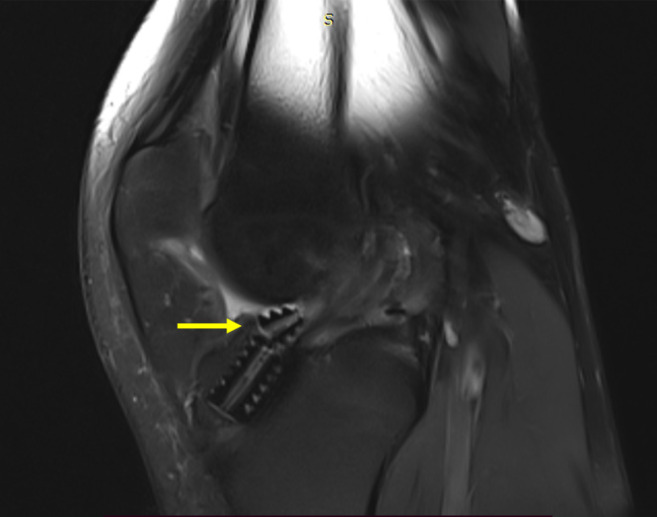

Case summary: A 26-year-old male presented with knee pain and swelling one year after ACL reconstruction using a hamstring graft and bioabsorbable tibial interference screw. The patient had been engaged in rigorous physical activity as part of military training. Clinical examination revealed mild effusion without instability, and imaging showed screw breakage with intra-articular migration. Therapeutic arthroscopy confirmed intact graft tension, and broken screw fragments were removed successfully. The patient resumed normal activity two weeks after surgery.